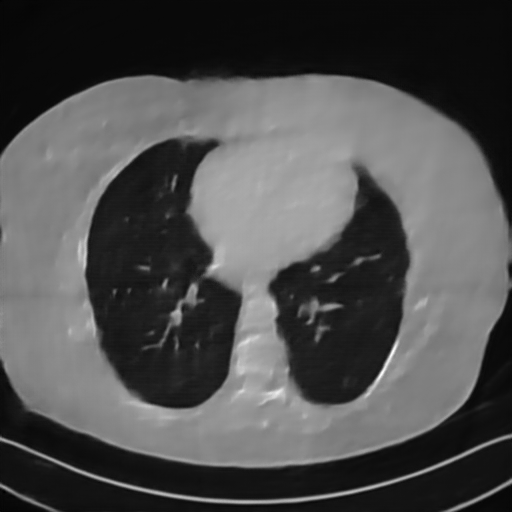

Fig. 4 presents the reconstruction results and residual images obtained by different methods for limited-angle reconstruction. As can be seen, the learning-based methods outperform the direct method and TV model, which exhibit serious artifacts in the missing angle region. Although the denoiser introduced by the FBP-Unet can somehow deal with the noises, the result still presents obvious artifacts. Compared to the SIPID, PD-net and FSR-nets, our LRIP-net1/2 can better preserve the image details and edges with less information left in the residual images. Thus, both the quantitative and qualitative results confirm that the low-to-high double-resolution strategy can improve the reconstruction accuracy for the limited-angle reconstruction problem.

We further increase the noise level contained in the raw data to 10% white Gaussian noises and list the quantitative results in Table IV. It can be observed that the reconstruction performance of the TV model is poor in the case of high-level noises with PSNR dropping by 4 to 5 dB compared to the previous experiments. On the other hand, the performance of the learning-based methods is less sensitive to noises. The SIPID method relying on the sinogram interpolation works better than FBP-Unet. And the deep unrolling methods (i.e., PD-net, IFSR-net, SFSR-net) outperform the traditional iterative algorithm when the scanning range is limited and data is corrupted by noises. Similar to the previous experiments, compared with other deep learning algorithms, our LRIP-nets give the reconstruction results with higher PSNR and SSIM. Moreover, the low-resolution image obtained by the projection data down-sampled with rate 1/8 always gives the best reconstruction results with more than 2 dB PSNR and 0.05 SSIM increments compared to the PD-net. Fig. 6 illustrates the reconstructed images from different methodologies with scanning angular range of and 10% Gaussian noises. It can be seen that the both TV model and the FBP-Unet suffers from significant artifacts, which present distortions in the angular range of the missing scan. Other learning-based methods provides better visual qualities than FBP-Unet, and our LRIP-net1/8 still gives the best reconstruction result with correct boundaries and fine structures.

Fig. 7 manifests the reconstruction results of these methods with scanning angular of . It can be seen that both FBP and FBP-Unet produce serious artifacts within the range of missing angles. The TV model performs well in removing Poisson noises, but it can not handle the artifacts very well. Similarly, there left obvious artifacts on boundaries and different degrees of missing in visceral tissues of the reconstruction images obtained by the SIPID, PD-net and FSR-net. The visceral tissue and boundaries of our LRIP-net reconstructions are more intact and smoother, especially for the LRIP-net1/8 which gives the ideal boundaries. The observation becomes even apparent if we look at the zoom-in regions, where the LRIP-nets can produce results with fine structures. Therefore, we conclude that the low-resolution image prior can effectively improve the qualities of the limited-angle CT reconstruction.